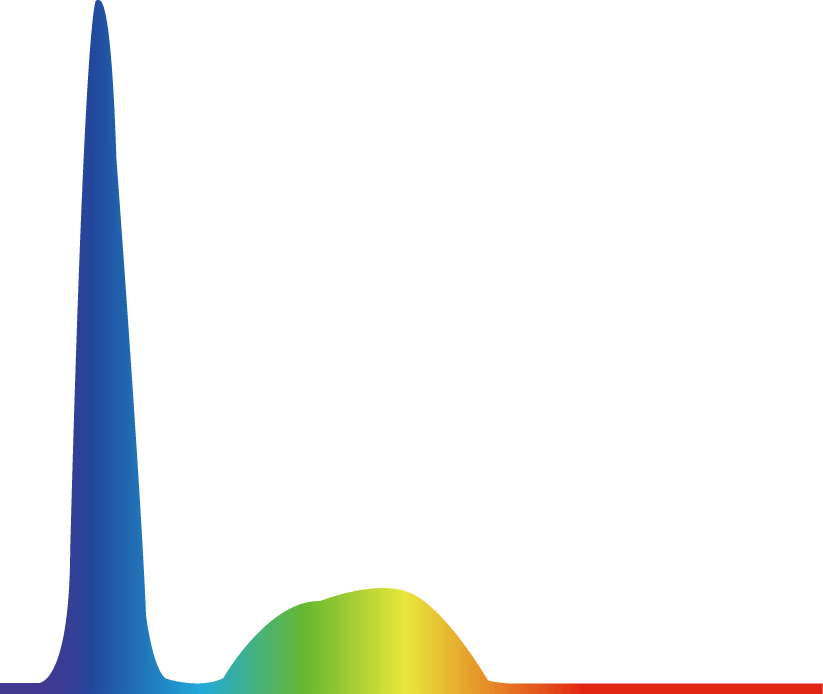

提供两种冷光源选择方案,氙灯更亮更接近自然光,呈现图像效果更真实、更有层次感。LED灯寿命长更经济环保,且提供多光谱输出,可提高微小病变的检出率。

氙灯

LED灯